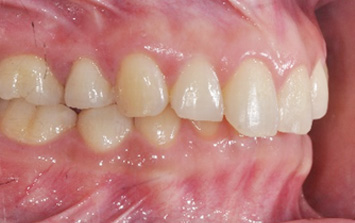

윗니가 아랫니를 과도하게 덮고 있는 과개교합 환자분. 과개교합의 경우 윗니가 아랫니에 가해지는 힘과 압력이 있어 턱 관절 및

근육 손상이 되기 때문에 반드시 교정치료가 필요합니다. 환자분의 경우도 아래 앞니 윗면이 닳아 있고 치아가 시린 상태. 클리피씨와 미니

스크류를 이용하여 위 치열 후방이동 하는 교정을 진행하였습니다.

위 치열 후방이동으로 앞니의 치아 물림이 개선되었고, 앞니의 시림 증상도 사라졌습니다. 과개교합의 경우 환자 스스로 눈치 채지 못하는 경우가 많고,

사각 턱 안모가 동반되는 경우가 많기 때문에 꼭 정밀 검사를 받아보는 것이 좋습니다.